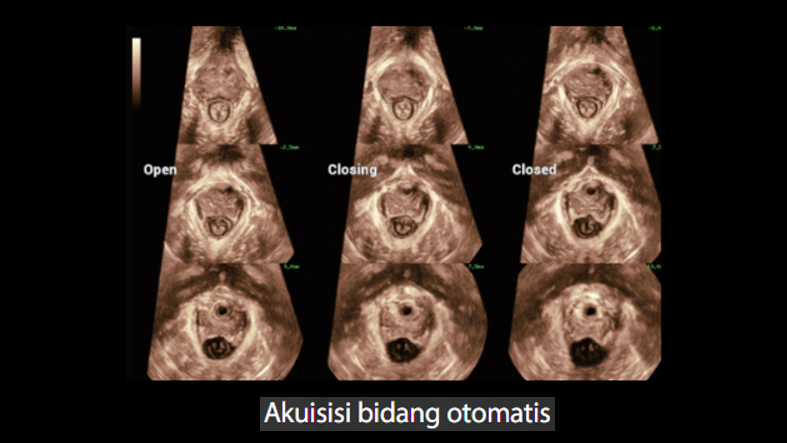

Gambar Klinis